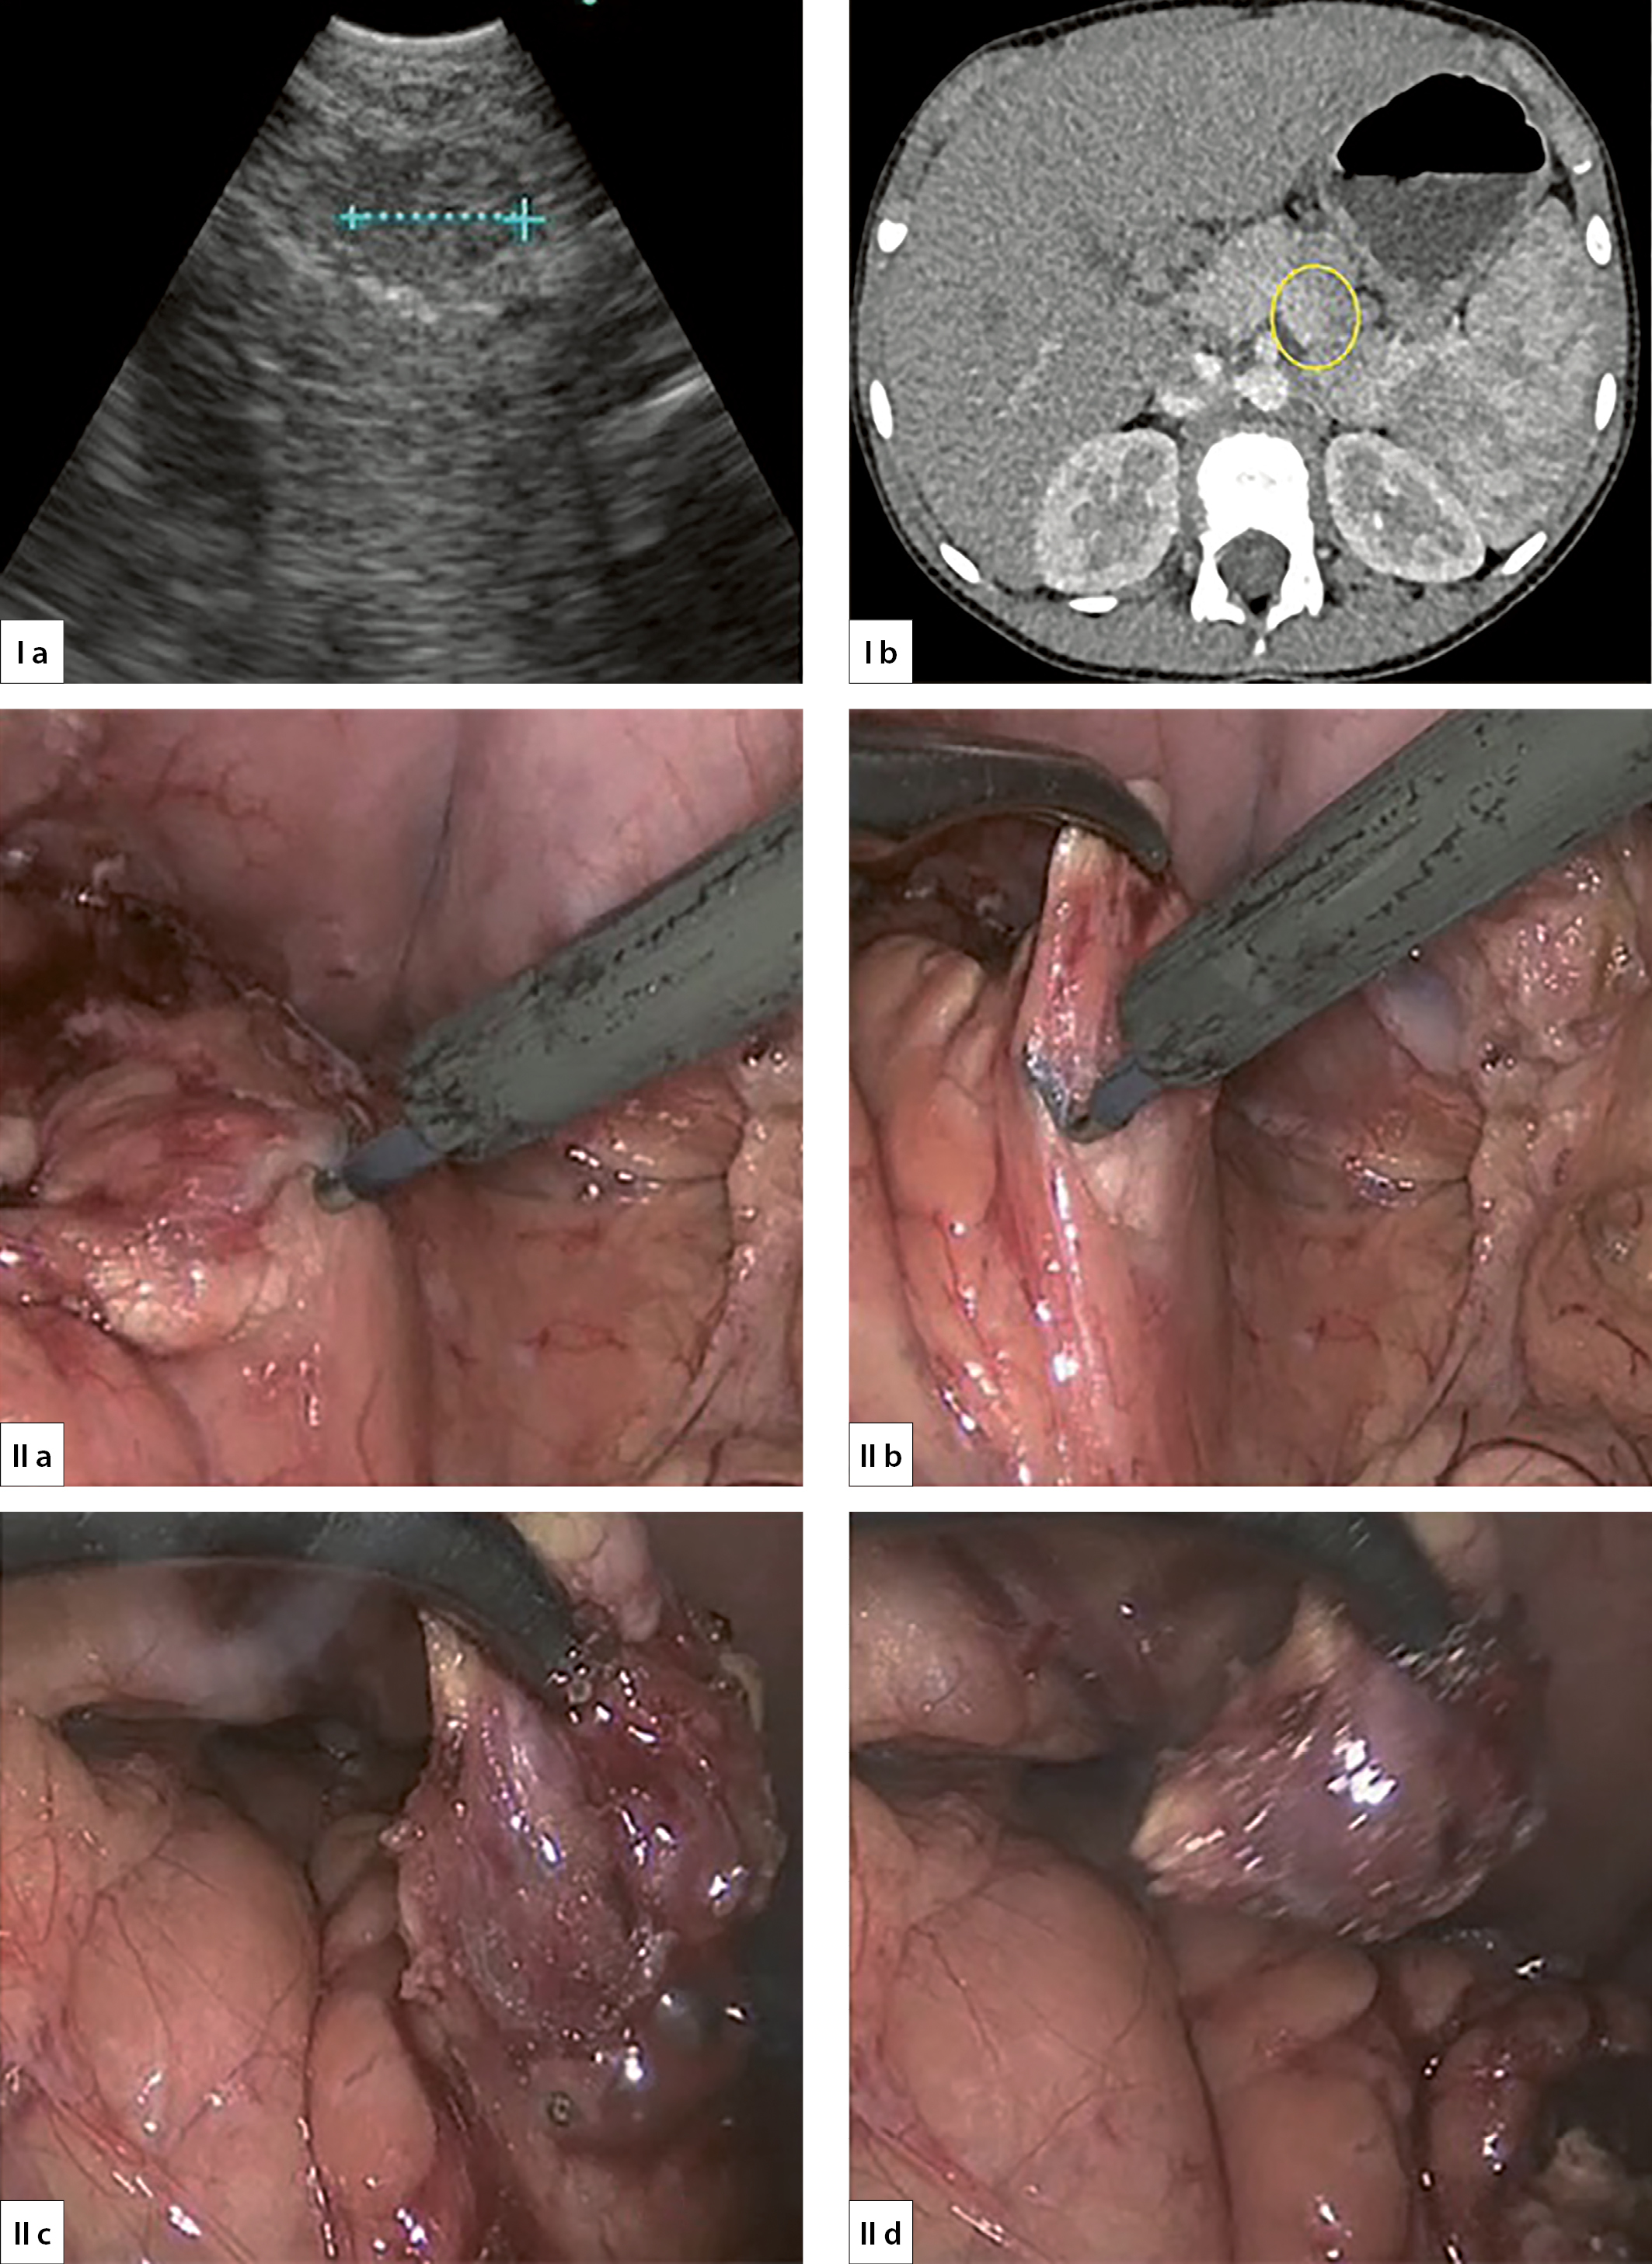

1. Рисунок 1. Лапароскопическая энуклеация инсулиномы ПЖ (I a — УЗИ инсулиномы в области тела ПЖ, I b — КТ инсулиномы в области тела ПЖ, II a — вскрытие заднего листка брюшины, II b, II c — выделение инсулиномы, II d — энуклеация инсулиномы).